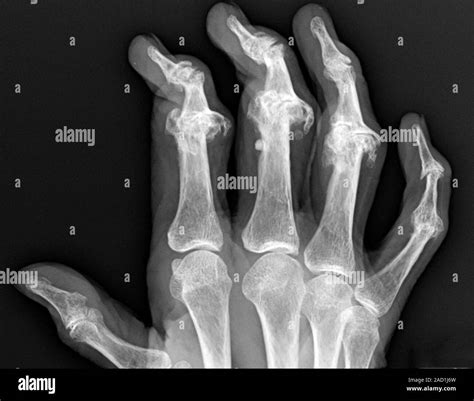

Psoriatic arthritis of the hand. X-ray of one of the hands of a woman with psoriatic arthritis ...

Other forms, such as psoriatic arthritis or post-traumatic arthritis (resulting from a previous injury), can also affect the hands, though they are less frequent than OA and RA.